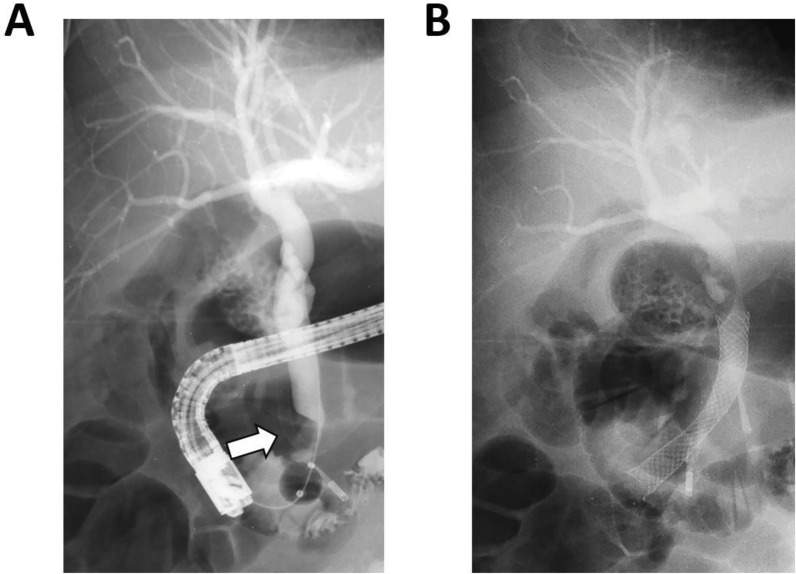

Hepatic artery aneurysms (HAAs) are rare vascular malformations that can arise from atherosclerosis, trauma, or iatrogenic injury. HAAs can be symptomatic and lead to serious complications. We present the case of a patient with painless jaundice caused by obstruction of the distal common bile duct by a HAA on a replaced right hepatic artery. This was further complicated with cholangitis. After endovascular stenting of the aneurysm, cholestasis decreased. Learning point: Hepatic artery aneurysms can cause common bile duct obstruction resulting in cholestasis.